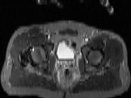

Visible Human male: Sectio transversalis 1876

CT

NMR

Pd                          / T2 \                         T1